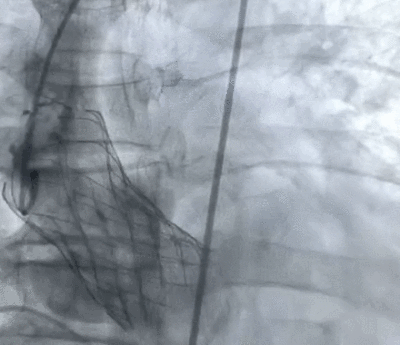

术后造影

主动脉CT检查诊断:三叶瓣,收缩期测得瓣环周长是84.2mm,左室流出道周长88.7mm(瓣下4mm),升主周长115.9mm(瓣上45mm);舒张期测得瓣环周长是83.1mm,左室流出道周长88.1mm(瓣下4mm),升主周长114.1mm(瓣上45mm);最终决定植入TAV30瓣膜。

术后即刻:微量瓣周漏,舒张压明显改善至69mmHg。